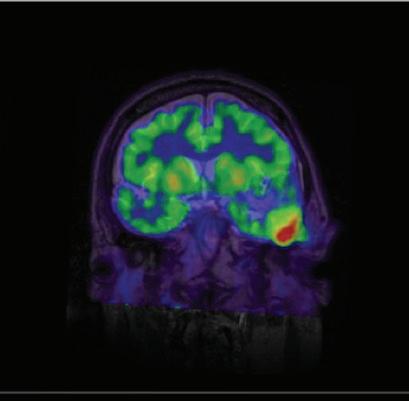

Dr. Zürcher Wimmer and team have begun to address this relative lack of understanding. Previous studies had found altered levels of a mitochondrial protein, TSPO, in males with ASD. In the present work, the first of its kind, the researchers used the advanced PET-MRI technologies in the Martinos Center with the [11C]PBR28 radioligand to measure TSPO levels in adult females with the disorder.

Their findings were striking. PET-MRI scans in 12 adult females with ASD and 10 healthy controls showed higher TSPO levels in specific brain areas in the former than in the latter. No brain areas in the females with ASD had lower TSPO levels. This contrasted sharply with previous findings in males with ASD, which showed generally lower TSPO levels than in healthy controls.

This has important implications for understandings of ASD. “Given the connection between TSPO and neuroimmune function, the findings suggest that neuroimmune mechanisms may be involved in autism,” Dr. Zürcher Wimmer says.